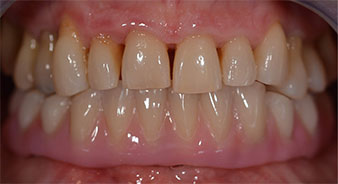

Пациентката е 64-годишна жена с частично обеззъбяване на зъби 38, 33 и 43 и частична долночелюстна протеза (Фиг. 1 и 2).

След това е взет отпечатък и е определена захапката на пациента, за да може зъботехникът незабавно да започне изработването на временната протеза. Протезата е поставена в същия ден (Фиг. 17 и 18).

След изчакване на необходимото време за осеоинтеграция, финалният отпечатък на имплантите е свален и следователно е изработена финалната протеза (Фиг. 19 и 20). В този момент, лекарят по дентална медицина и пациентът могат да обсъдят дали да използват керамични или пластмасови фасети и циркониева или метална рамка. В този случай, екипът на д-р Паску избира пластмасови фасети, имайки предвид неясната прогноза относно частичното обеззъбяване в челюстта и фактът, че зъб 24 е прорастнал. Този вид протеза обикновено е по-лесна за адаптиране и впоследствие може да бъде променяна спрямо новата ситуация в челюстта.